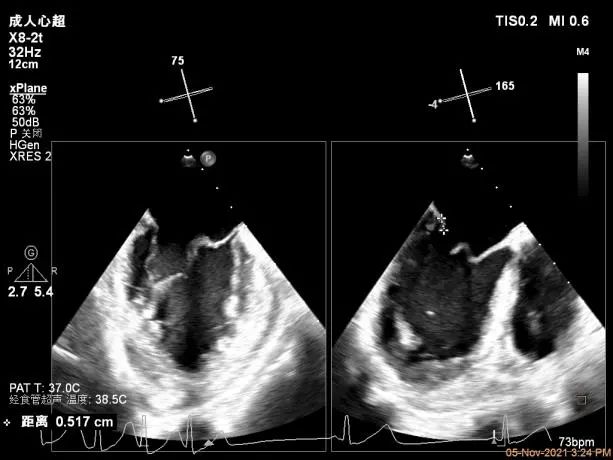

术前超声评估结果

术前超声诊断

二尖瓣瓣环前后径26mm,左右径26mm

Bicom:MR(重度),返流束宽12.5mm,返流面积11.4cm²

PISA法定量EROA:0.74cm²,Rvol:118ml,RF:63%

右上肺静脉血流频谱呈收缩期反向

3D MV View:A2/A1区脱垂

3D-color MV view:血流主要来源于A2区,少部分来源于A1区

Qlab软件勾画估测瓣口面积约:5.6cm²

二尖瓣口平均跨瓣压差:4mmHg

TEE Bicom view:主要脱垂区域为2区

Color-view:返流束主要来源于2区脱垂

A1P1区后叶发育短小,约5.3mm

A2P2区前后叶长度可,为主要脱垂区域,进而制定手术策略: 2区一个长夹子解决脱垂主要病变区域